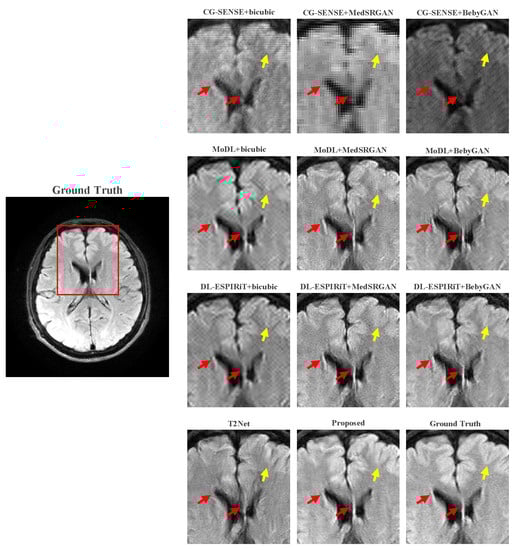

For a more intuitive comparison, we provide visual comparisons for each method. In Figure 5 and Figure 6, we illustrate the axial and sagittal views of the 2D brain dataset, respectively. In Figure 7 and Figure 8, we display the brain image and neck image of the 3D VWI dataset. For each method, we show the restorations along with the corresponding error maps. The images are placed on the left, the error maps on the right, and the PSNR and LPIPS metrics of each image are shown at the bottom right corner. From the error maps, it is evident that our proposed method consistently produces high-quality results with improved visual fidelity and better retention of structural information compared to the other methods.

Figure 9 and Figure 10 present the zoomed-in images of the enclosed parts in the ground truth. Our proposed method can faithfully recover the fine structures, as indicated by the red arrows, and successfully preserve the image contrast, as pointed out by the yellow arrow. The high-fidelity restoration achieved by our method in these zoomed-in regions further demonstrates its ability to faithfully recover fine details and enhance image quality.

Figure 10. Zoomed-in view of the VWI dataset comparison experiment.